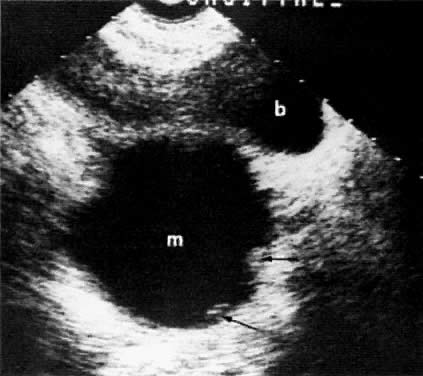

Ultrasound also plays a very limited role in ovarian tumor staging. The staging accuracy of ovarian neoplasms by ultrasound is poor (48%). Pelvic ultrasound examinations can show the size and local extent of the tumor, involvement of the contralateral ovary, uterine or bladder invasion, and local peritoneal spread. The presence of a uterus inseparable from an ovarian mass (Fig. 35B and Fig. 35C) correlated with uterine involvement in 74% of the cases, whereas the presence of a uterus separable from an ovarian mass correlated with a lack of uterine involvement in 93% of the cases.77

Fig. 35. Ovarian adenocarcinoma involving both ovaries ( o) and uterus ( u) with ascites ( a ). CT scan of the pelvis ( A) shows bilateral ovarian masses with ascites and uterine involvement on the left. Transverse ( B) and sagittal ( C) sonograms of the pelvis in a different patient show large, bilateral, irregular, and inhomogeneous ovarian masses inseparable from the uterus. Ascites is seen on the sagittal scan. The CT and ultrasound findings are consistent with at least stage II. ( b, bladder.)